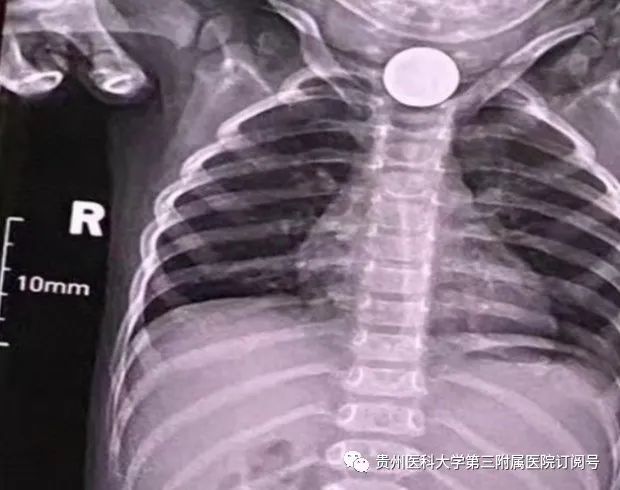

当晚9点多,小语(化名)被家人送到了我院消化内科,家长告诉接诊医生吴国娣,小语好像吞食了异物,哭闹且一直呕吐。接诊后,经DR检查发现食管上段可见类圆形致密度阴影,初步判断为误吞了硬币。由于硬币刚好卡在食管上段,从喉部根本看不清。